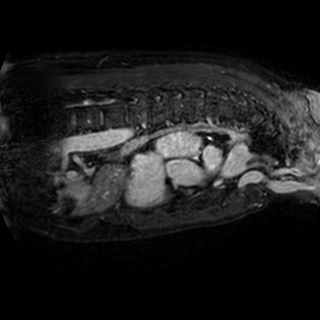

The integration of deep learning systems into healthcare has been hindered by the resource-intensive process of data annotation and the inability of these systems to generalize to different data distributions. Foundation models, which are models pre-trained on large datasets, have emerged as a solution to reduce reliance on annotated data and enhance model generalizability and robustness. DINOv2 is an open-source foundation model pre-trained with self-supervised learning on 142 million curated natural images that exhibits promising capabilities across various vision tasks. Nevertheless, a critical question remains unanswered regarding DINOv2's adaptability to radiological imaging, and whether its features are sufficiently general to benefit radiology image analysis. Therefore, this study comprehensively evaluates DINOv2 for radiology, conducting over 100 experiments across diverse modalities (X-ray, CT, and MRI). To measure the effectiveness and generalizability of DINOv2's feature representations, we analyze the model across medical image analysis tasks including disease classification and organ segmentation on both 2D and 3D images, and under different settings like kNN, few-shot learning, linear-probing, end-to-end fine-tuning, and parameter-efficient fine-tuning. Comparative analyses with established supervised, self-supervised, and weakly-supervised models reveal DINOv2's superior performance and cross-task generalizability. The findings contribute insights to potential avenues for optimizing pre-training strategies for medical imaging and enhancing the broader understanding of DINOv2's role in bridging the gap between natural and radiological image analysis. Our code is available at https://github.com/MohammedSB/DINOv2ForRadiology